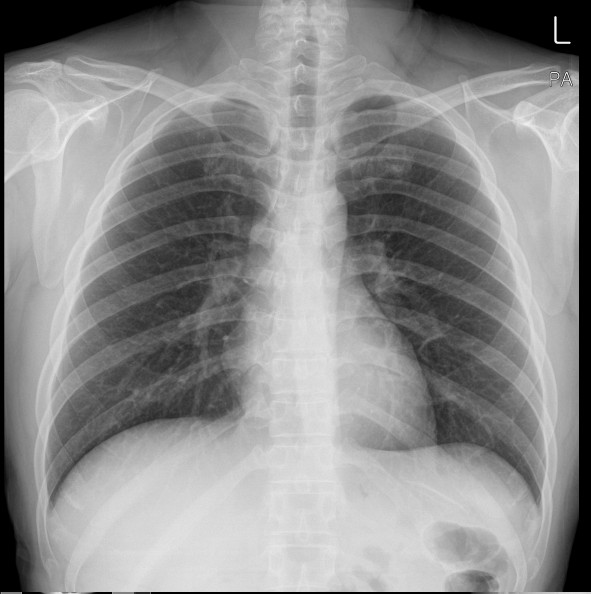

왼쪽 아랫배 통증은 다양한 원인에 의해 발생할 수 있으며, 통증의 양상(급성 통증, 만성 통증, 쥐어짜는 듯한 통증 등)과 동반 증상에 따라 의심되는 질병이 달라집니다. 다음은 왼쪽 아랫배 통증과 관련된 주요 질병 10가지입니다.